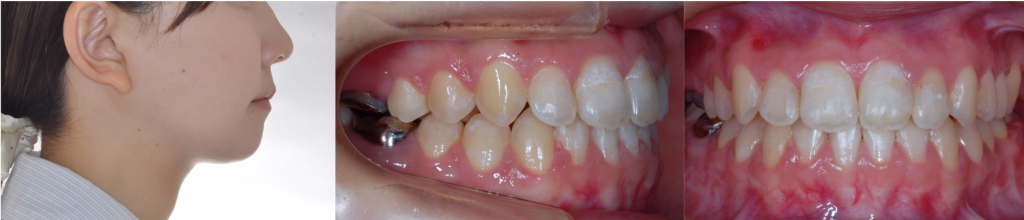

下顎骨切り手術後9日 22歳2カ月 退院時は顎間固定用のフックが付いています。1カ月後にはプレーンなワイヤーに交換します。